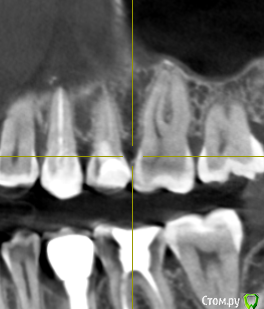

Добрый день! Два месяца назад началась моя история с зубами. Беспокоили дикие боли в зубах, как при пульпите, в 4-ке и 5-ке. Сделано было несколько прицельных и рентгеновских снимков, которые ничего не показали. Обошла пять стоматологов, никто проблем не находил, отправляли к лору или неврологу. КТ никто сделать не предложил, к сожалению. Было принято решение совместно с шестым! стоматологом депульпировать эти два зуба. При удалении нервов стоматолог сказал, что нервов уже почти нет и в 4, и в 5, сказал, что у меня хронический периодонтит, а в 4-ке стоматолог увидела на снимке (когда проверяла каналы после лечения) наружную резорбцию корня. В 5-ку поставили сразу постоянную пломбу, в 4-ке сейчас стоит временная (материал МТА). Но боль в 4-ке осталась, она не такая конечно сильная, как была, но ноющая, усиливается после горячего, после еды, в основном. И над зубом есть свищ, он не беспокоит и не болит при надавливании (стоматолог говорит, что это материал под десной, из-за резорбции) Врач говорит, что все пройдет, и через 2 месяца ставим постоянную пломбу, но болит уже месяц. Я сама сделала КТ, очень прошу вас посмотреть и подсказать, как действовать дальше? Может проще удалить этот зуб и поставить имплантат?